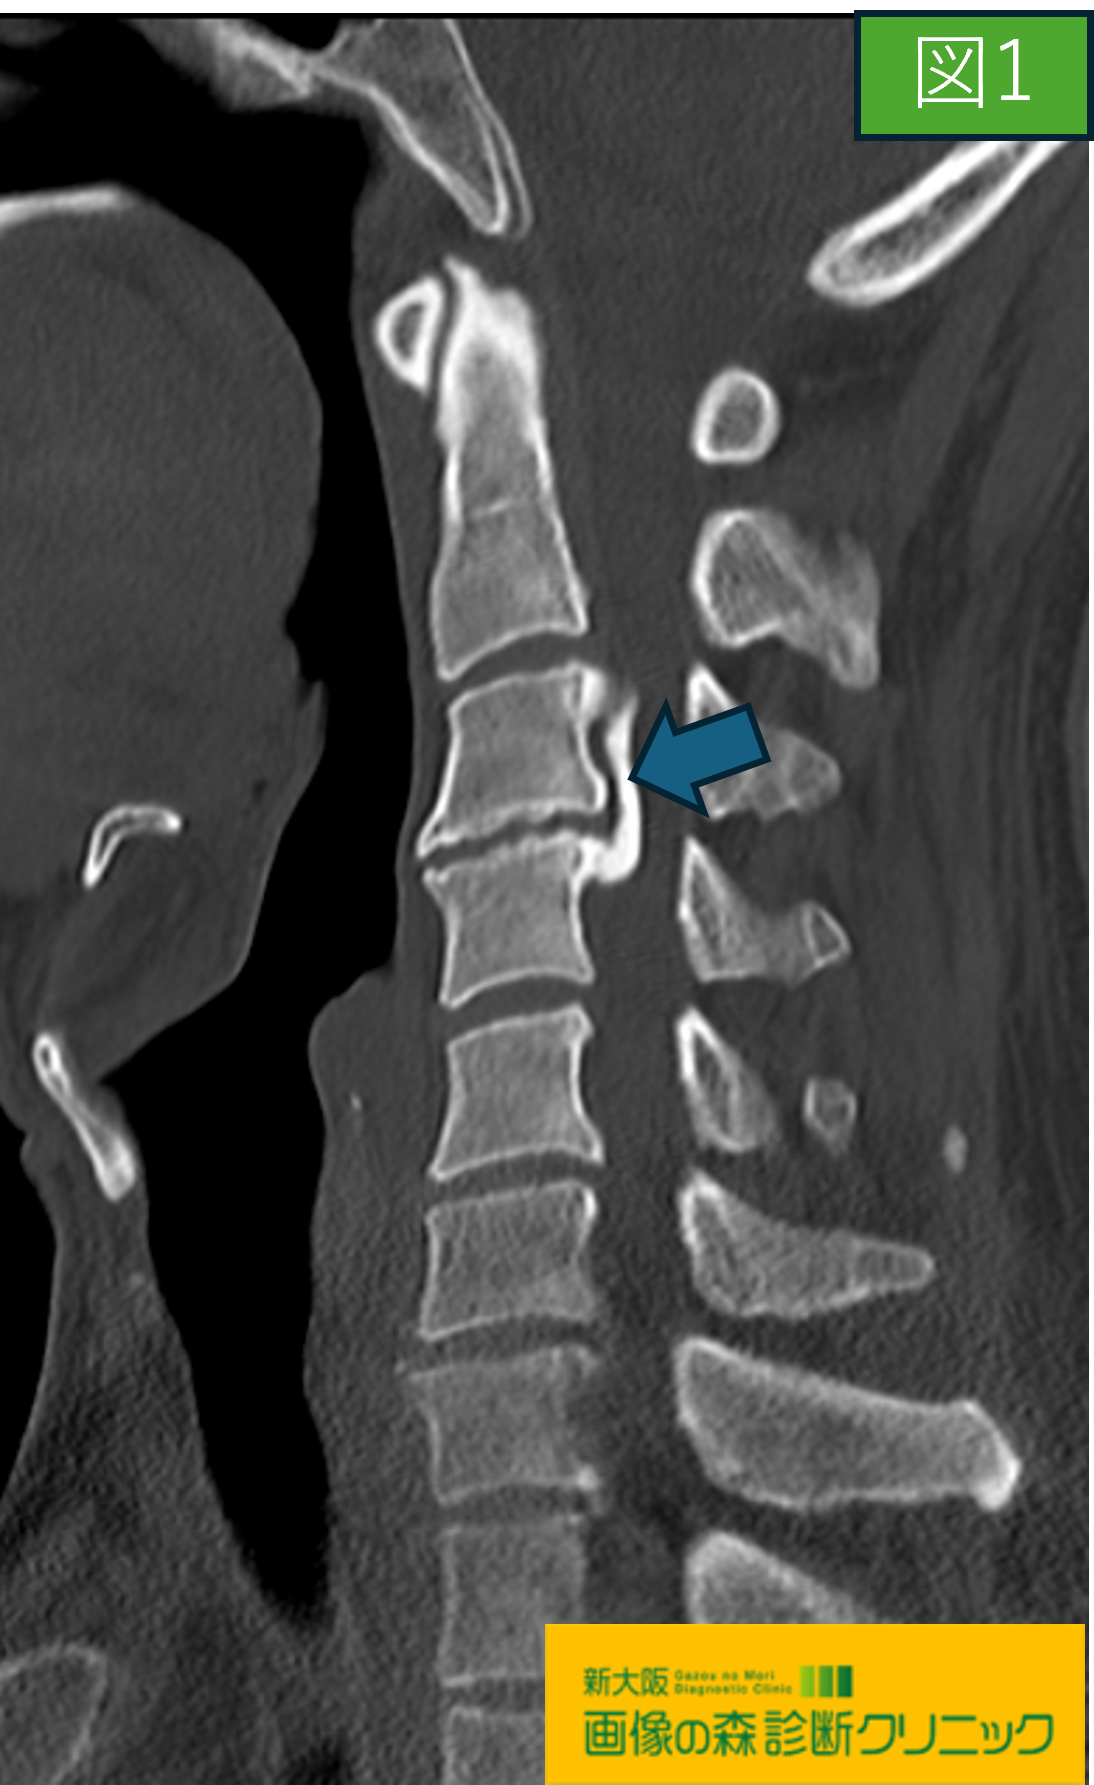

画像から図1・図2は頚椎CT画像です。

図1・図2はCTによる後縦靱帯骨化症を示しており、

脊柱管内の後縦靱帯を描出することができます。